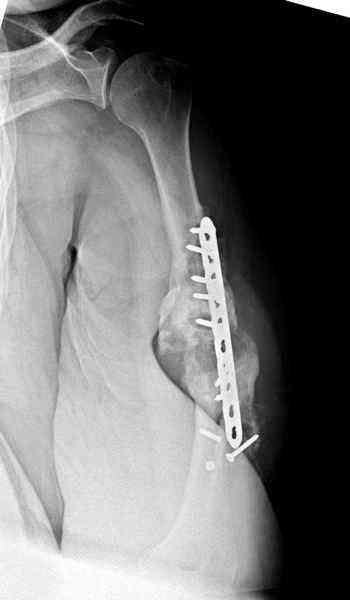

Помогите, пожалуйста, определиться с тактикой!Поступил больной с ложным суставом плечевой кости... Перелом был 2 года назад. Лечился в аппарате 8 месяцев, консолидации не произошло. В феврале 2007 выполнена костная аутопластика, фиксация пластиной (на базе одной из ИК). Сейчас сохраняется ложный сустав, плечо укорочено на 3 см, контрактура обоих смежных суставов, атрофия мышц плеча и плечевого пояса справа. Явлений остеомиелита не отмечалось. Больной - осужденный, сидеть ему до 2012 года.

Уважаемая Татьяна,

Как видно из выступлений коллег, способы фиксации

ложного сустава плеча могут быть различными, кто-то предпочитает аппаратом Илизарова (Соломин), пластинами (Волна) или интрамедуллярным гвоздем (Челноков).

Когда разбирался случай на сайте, и у нас была больная с похожей патологией, ложный сустав после поперечного перелома, леченного год назад где-то и кем-то в другом месте.

Мы не стали делать провокационный метод, который

предложил Корнеев для лечения - применение анаболических стероидов - ретаболила, из-за его бессмысленности, также не согласились с его теорией, что любая операция заблокирует суставы, а наоборот, провели жесткую фиксацию пластиной для раннего восстановления.

Первичную пластину убрали недели 6 назад из переднего оригинального доступа, и из-за подозрительности тканей вокруг пластины, решили провести реконструкцию поэтапно.

После промывки и дебридмента для уверенности уложили антибиотический цемент. Культура из раны в последующем была отрицательная.

Хотя сам не стороннник применения более массивных

имплантов для плеча, но для этого случая сделали

исключение. На снимке 4А диаметр мягких ткани около 20 см, при весе больной более 135 кг, и также выступление Андрея Волны подстегнуло к применению более массивной 4.5 мм локинг пластины.